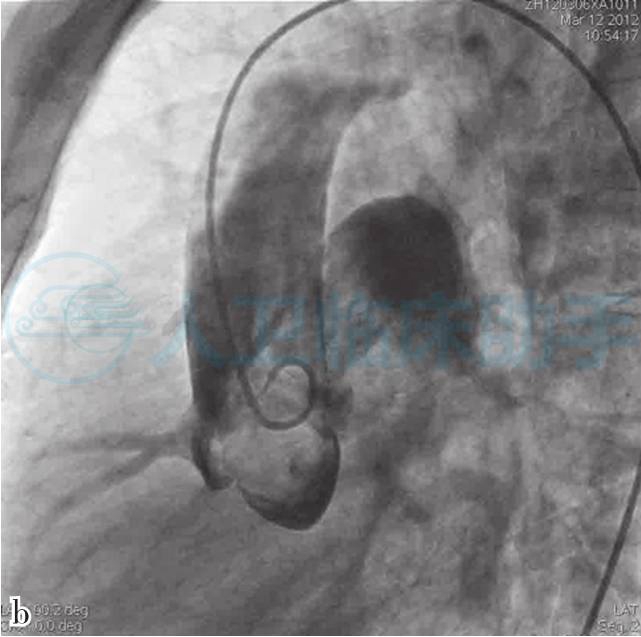

肺动脉造影(图3)诊断:右肺动脉起自升主动脉,动脉导管未闭,肺动脉高压(重度)。

图3 升主动脉造影正位(a)与侧位(b)显示右肺动脉起自升主动脉近段左后壁,导管测压证实右肺动脉压与升主动脉压一致